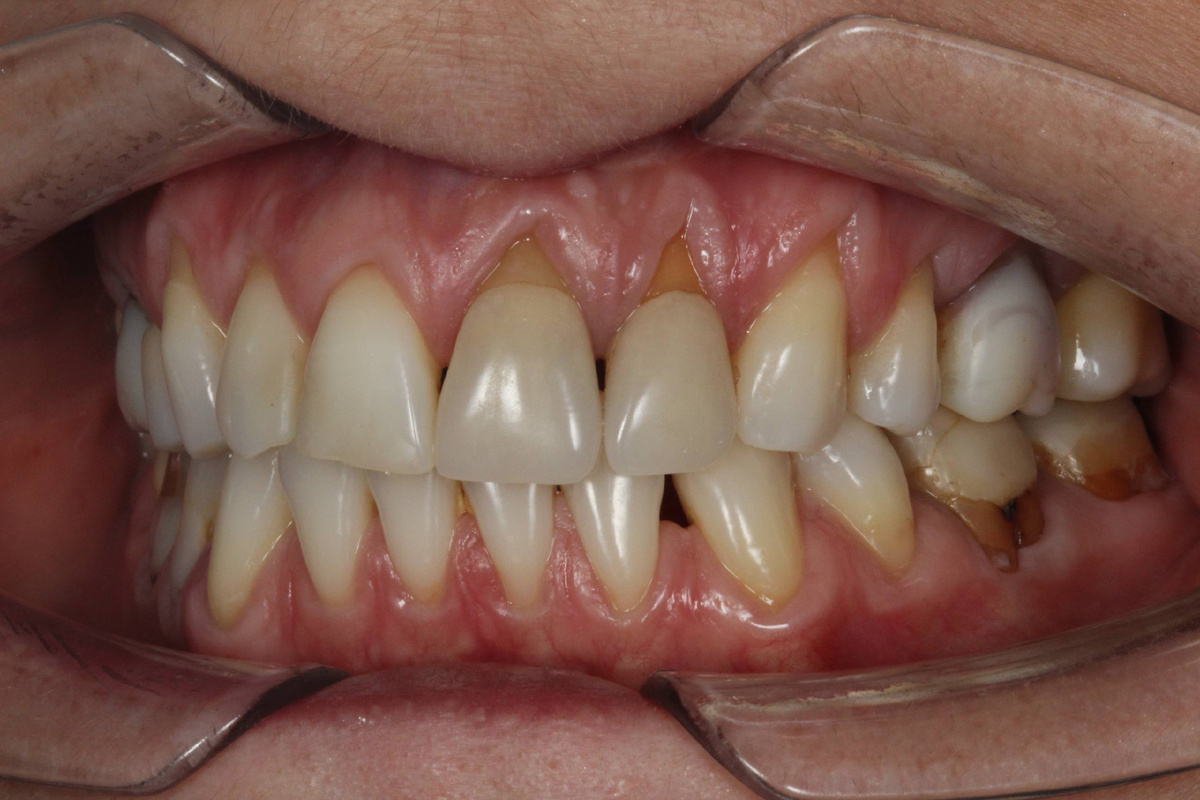

На фото рецессия у пациентки с патологией прикуса. Девушке 37 лет. Она прошла лечение у ортодонта и мы провели пластику десны. чтобы закрыть оголенные участки.